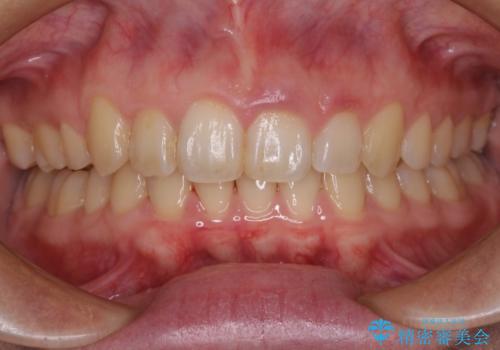

- 小さいころからの歯の変色と矯正治療の後戻りを気にして来院された患者様です。

気になる変色歯を仮歯に変え、その後歯列不正を矯正治療で改善し、最後にオールセラミッククラウンにて補綴治療することとしました。

数十年に及んだ歯の変色が改善されたため、大変満足していただきました。